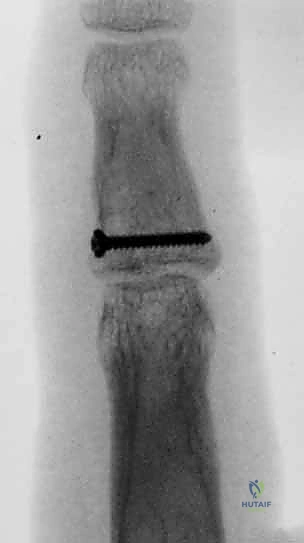

1. الرد المفتوح والتثبيت الداخلي (ORIF)

هذه هي الجراحة الكلاسيكية والمفضلة عندما يكون هناك قطعة عظمية واحدة كبيرة يمكن تثبيتها.

* الخطوات: يقوم الدكتور هطيف بعمل شق جراحي دقيق (عادة على شكل متعرج Bruner incision) للوصول إلى المفصل دون إتلاف الأوتار. يتم إرجاع العظم المكسور إلى مكانه التشريحي بدقة مجهرية.

* التثبيت: يتم تثبيت الكسر باستخدام مسامير تيتانيوم متناهية الصغر (Mini-screws بحجم 1.3 مم أو 1.5 مم) أو باستخدام أسلاك كيرشنر (K-wires). يضمن هذا التثبيت الصلب قدرة المريض على بدء تحريك إصبعه بعد أيام قليلة من الجراحة.